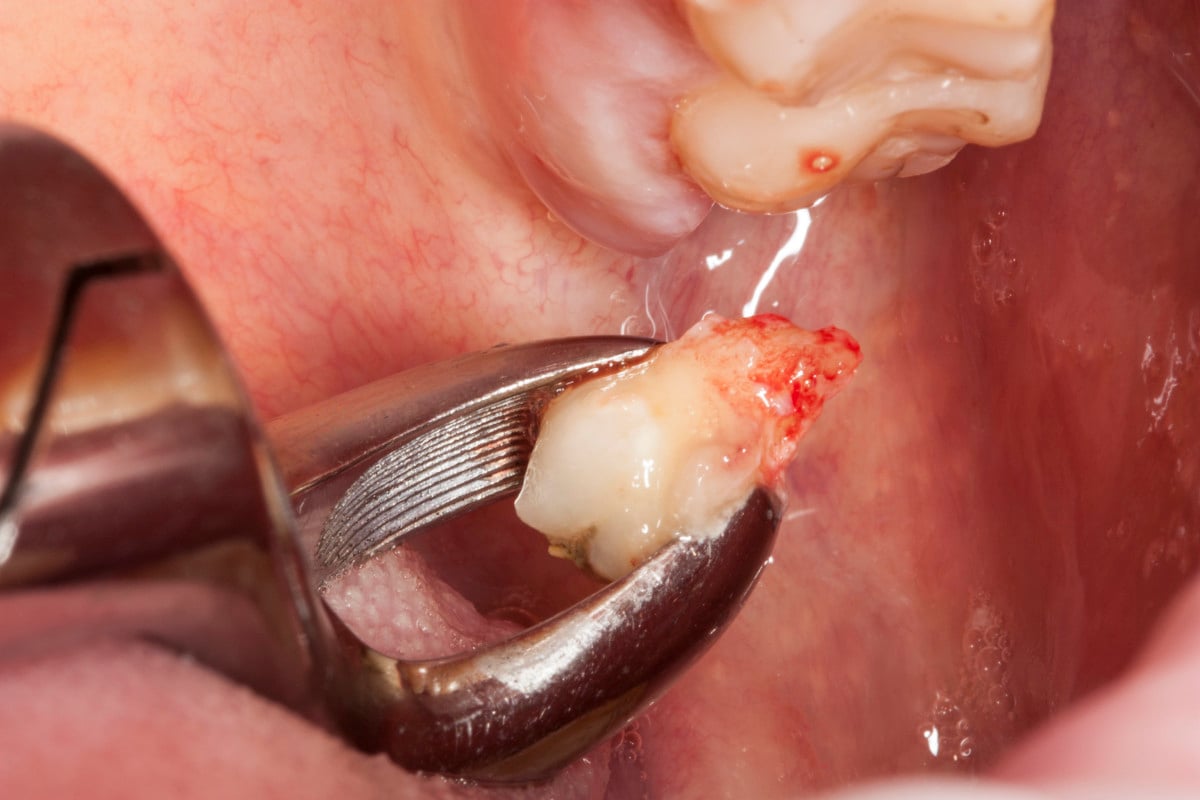

„Pacjent, który się zgłosił z dolegliwościami bólowymi górnej lewej szczęki, miał charakterystyczne objawy dla zapalenia ozębnej. Dzięki wykonaniu diagnostyki radiologicznej (zdjęcie pantomograficzne), ujawniono istnienie dziewiątego zęba, który był dodatkowo obciążony okluzyjnie. Pacjent miał otwarty zgryz – w momencie, kiedy zamykał zęby kontaktował się tylko na zębach trzonowych. To wszystko powodowało, że główny nacisk zębów był na tą malutką stożkową dziewiątkę. Przeciążenie tego zęba spowodowało to, że związanie włókien kolagenowych z podłożem kostnym osłabiło się, powstała kieszeń dziąsłowa i kieszeń kostna. To wszystko było przyczyną silnych dolegliwości bólowych o charakterze periotonditis, czyli zapaleniu wzdłuż calej długości ozębnej.

Pomimo, że ten ząb umieszczony w guzie szczęki, w miejscu bardzo odległym, niewidocznym i pacjent nie miał świadomości, że ma ząb dziewiąty, to zabieg był dość prosty, nie sprawiający kłopotów i nie wystąpiły żadne komplikacje.” –